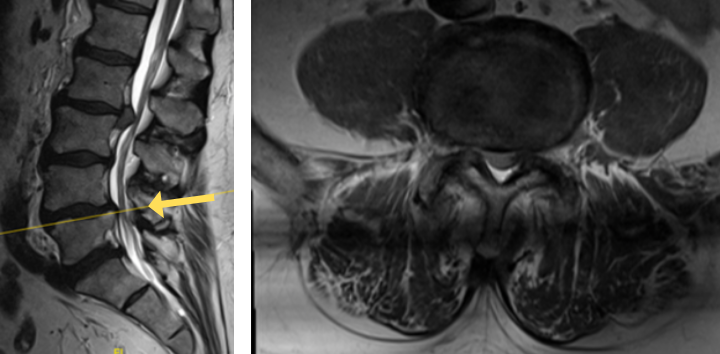

The grade 1 spondylolisthesis at L4/L5 requires both decompression at the L4/L5 level but also fusion because of the instability with motions. Here are three standing x-rays: one in the neutral position, one in flexion, and one in extensions. Notice the movement in the vertebral bodies at L4 and L5. This is abnormal motion and it can contribute to back pain and increase stenosis in certain positions. Thus, it requires decompression and stabilization with fusions.

Image 2. This shows the lumbar spine in motion. Notice the L4 and L5 level changes with flexion and extension. Notice the L2 and L3 levels do not have that type of motion. This is instability.

The herniated disc only requires decompression and removal of the herniated disc. Notice in the same flexion extension dynamic x-rays. There’s no abnormal motion at the L2/L3 level.